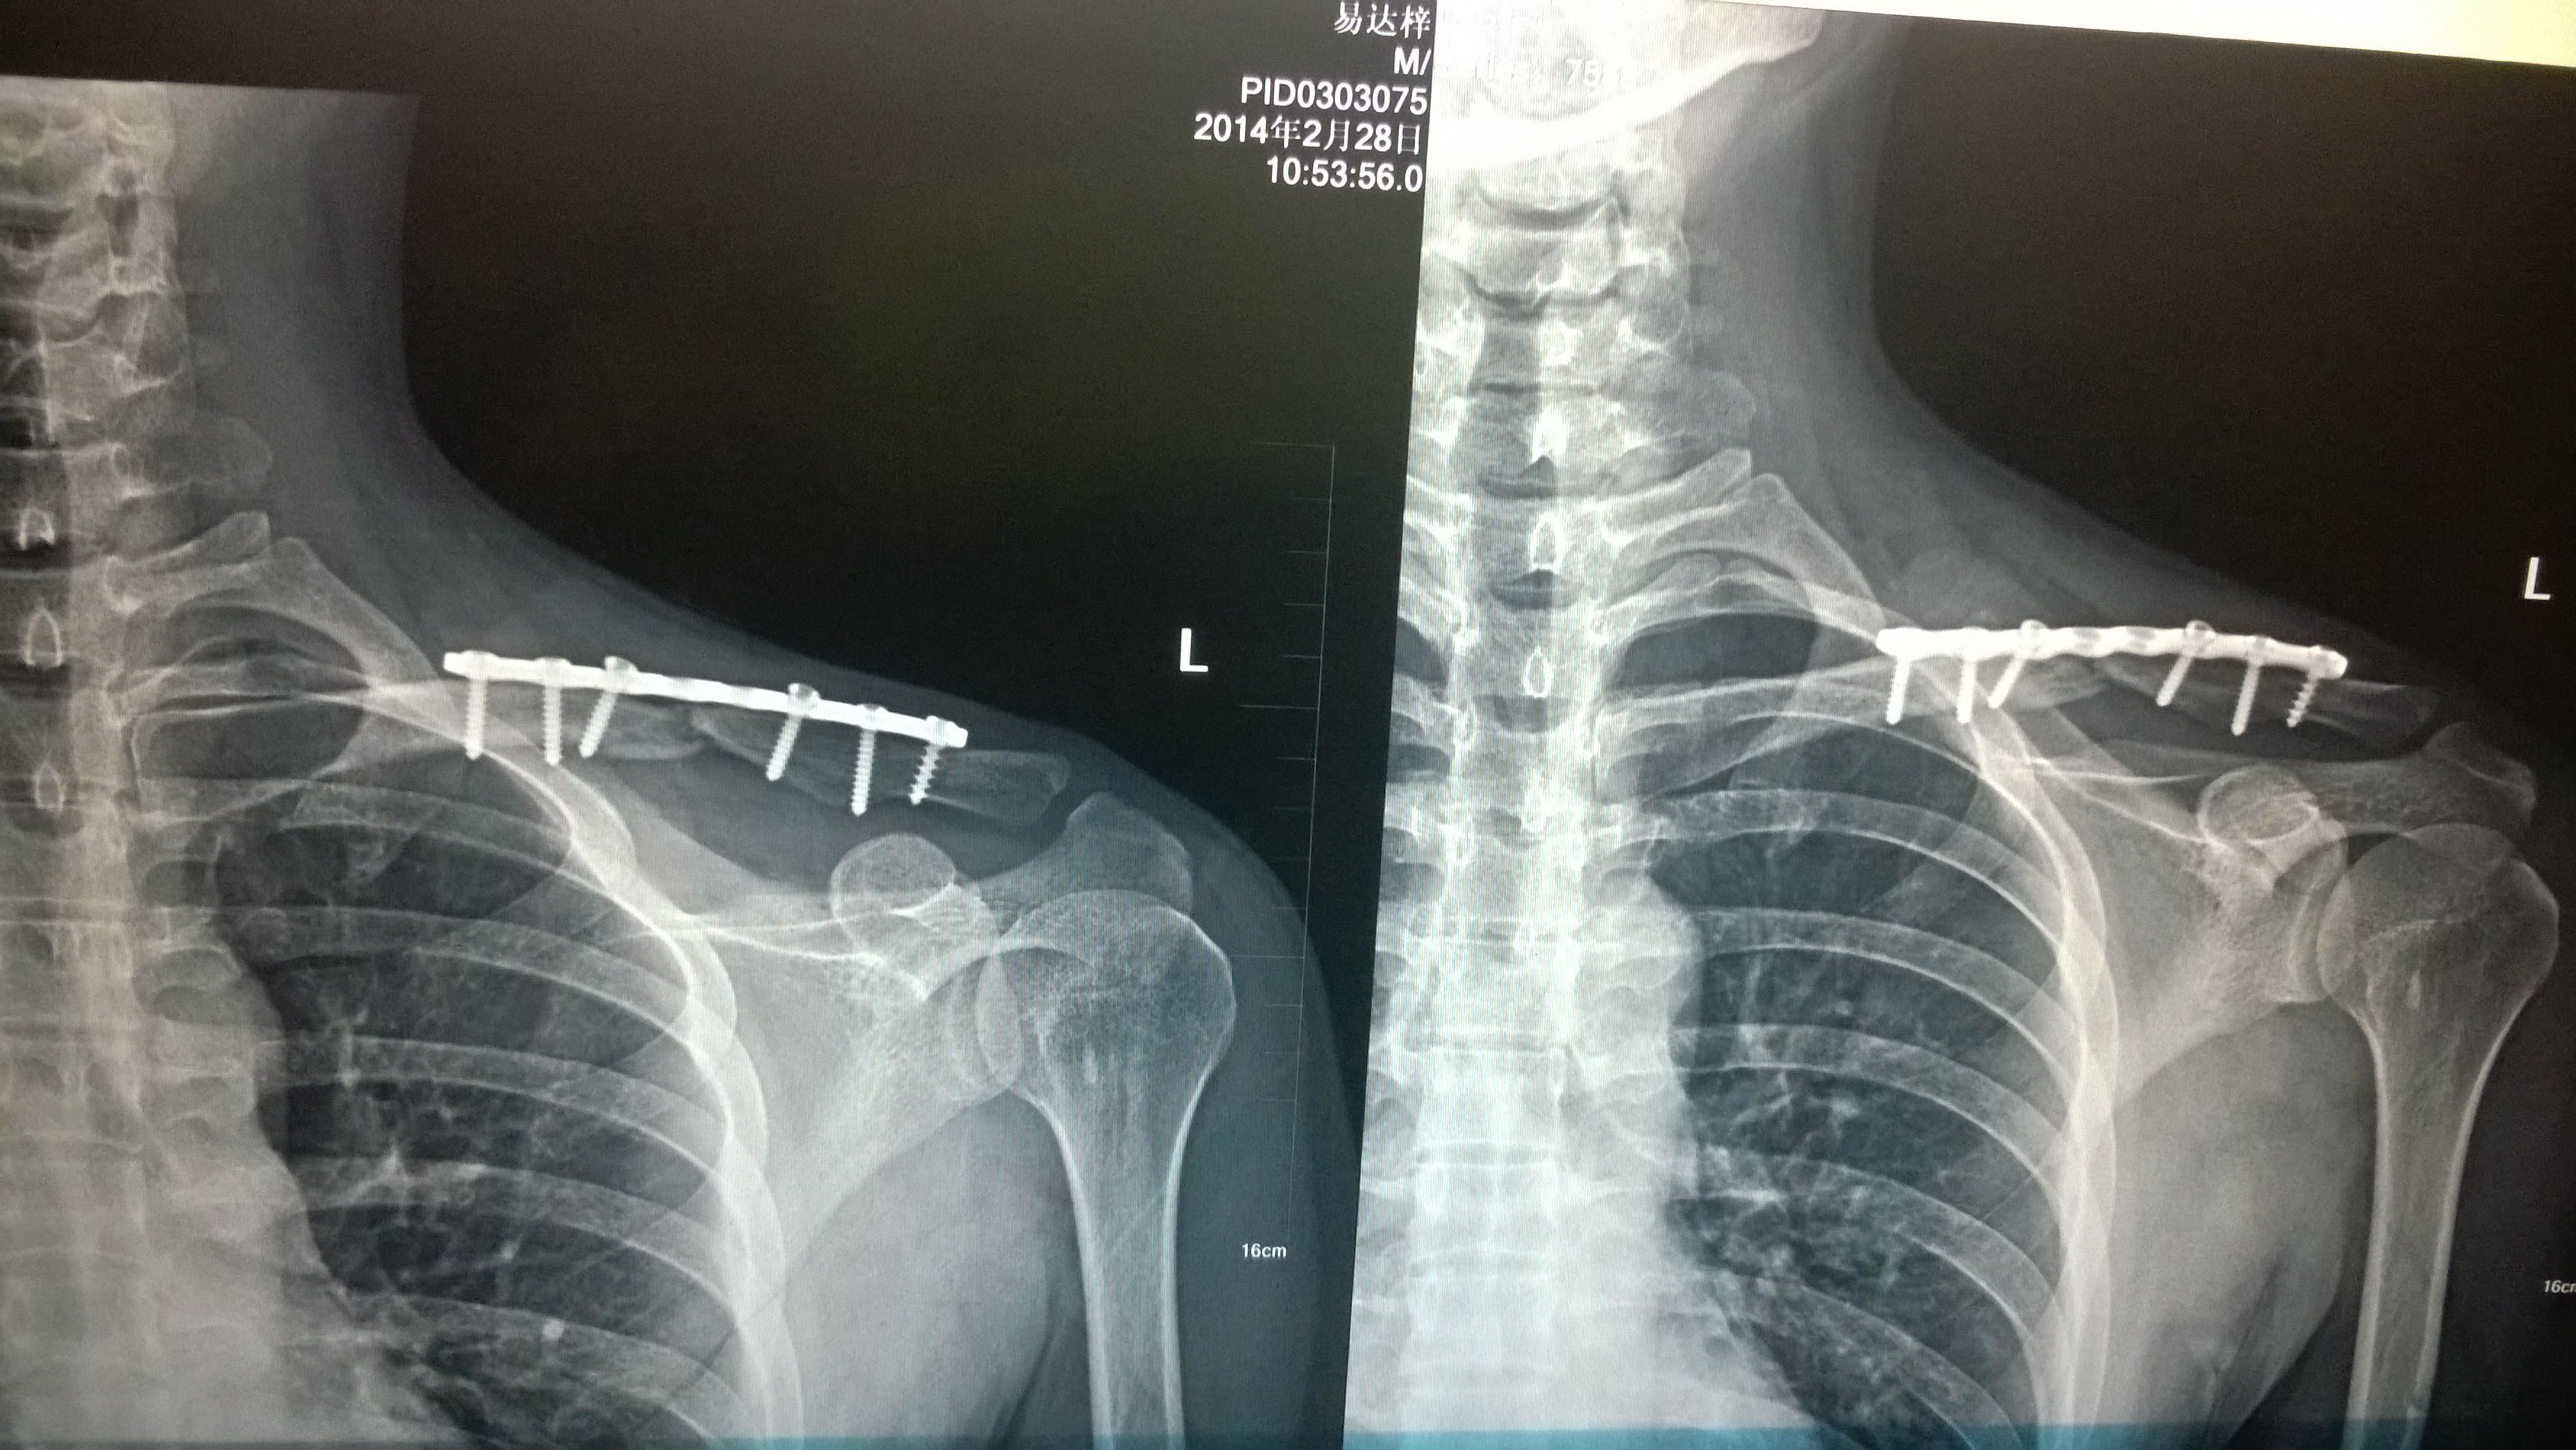

锁骨骨折术后3个月才开始运动的,但现在术后10个月才发现骨头还没长好,还能痊愈吗?概率多大?

医师要我2个月后再来拍片,还没长好就要植骨,现在好好休养2~3个月能痊愈吗,这种情况是不是晚期了,痊愈概率大吗?

病情分析: 你的骨折内固定以后,对位是可以的,但是没有骨痂形成。 指导意见: 如果十个月了没有愈合,应该在休息2-3个月也不会愈合的。应该采用植骨的方法进行治疗。